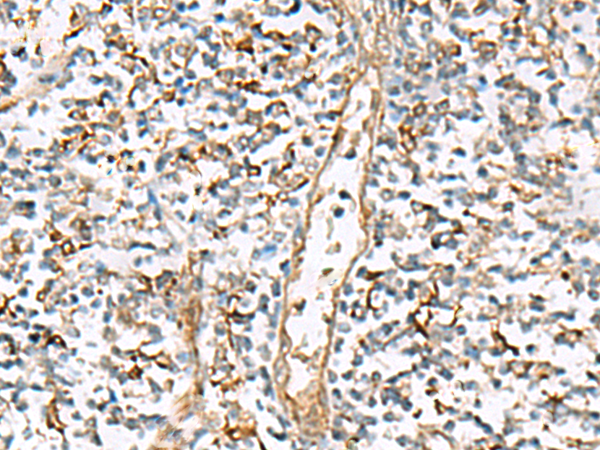

IHC positive control: |

Human liver cancer and Human prostate cancer |

IHC Recommend dilution: |

25-100 |